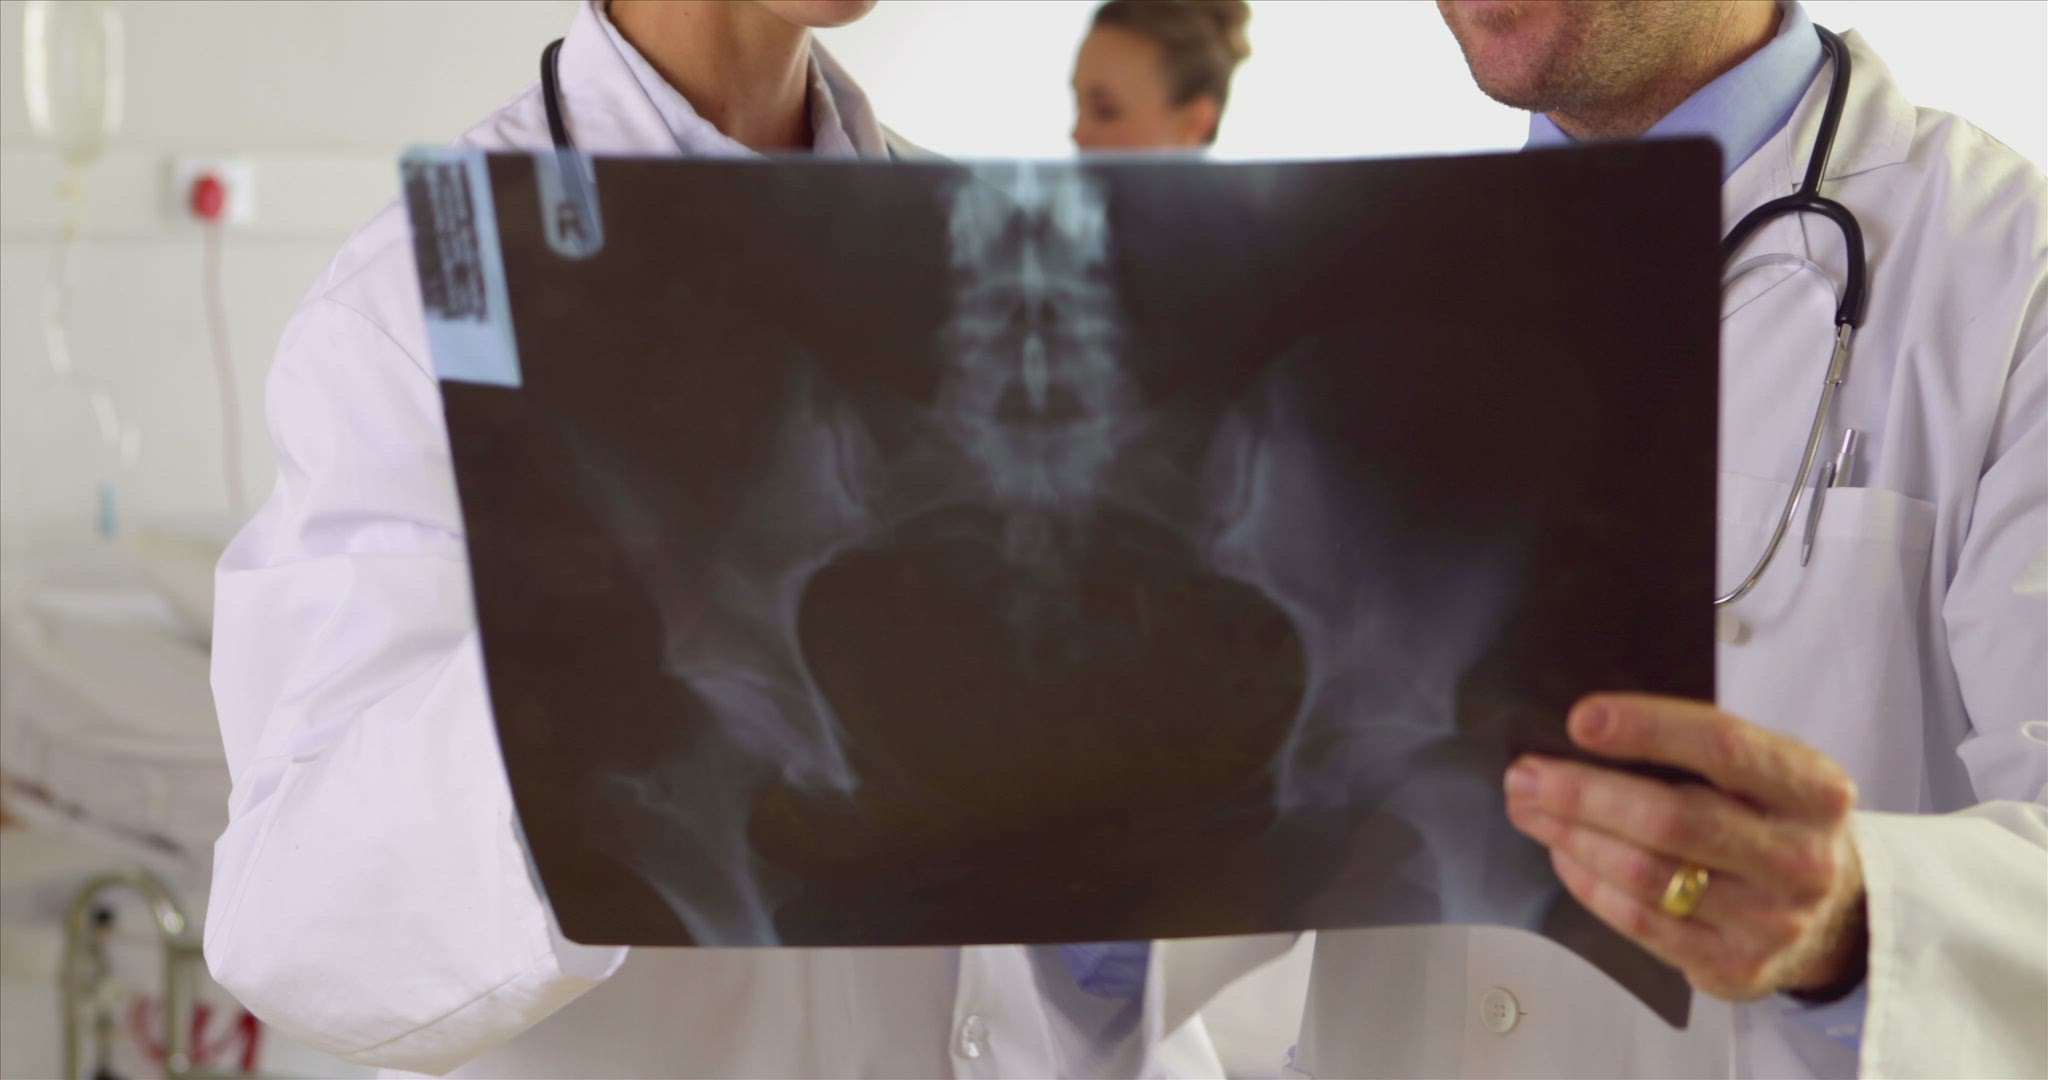

1928061 - 883781050 / Specialist / Doctor / Medical Staff

1928061 - 883781050 / Specialist / Doctor / Medical Staff